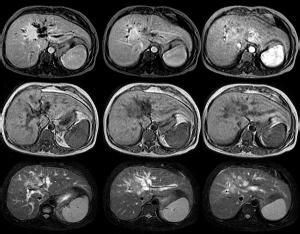

3. 磁共振膽管成像(MRCP)與超聲及CT比較有明顯的優勢。

①具有非侵入性、無創性、無放射性、無需對比、病人易接受;

②可以清楚的顯示整 膽管的情況,對臨床分期和術前評估更準確;

③安全,無併發症;

④不能行經內鏡逆行胰膽管造影(ERCP)檢查或ERCP檢查失敗者可行MRCP檢查;

⑤可以指導經皮經肝穿刺膽道引流(PTCD)和膽管內支架放置的位置。

肝門部膽管癌MRCP主要表現為肝總管、左右肝管起始部膽管壁不規則增厚、狹窄、中斷或腔內充盈缺損;肝門軟組織腫塊,向腔內或腔外生長,邊界欠清晰,T1加權呈相對低信號,T2加權呈相對高信號;腫瘤上方肝管呈軟藤狀擴張,腫瘤下方膽總管正常,並可顯示膽囊管和胰管情況。如有肝門部淋巴結轉移,CT和MRI表現為肝門部腫塊,而MRCP表現為左右肝管受壓變窄或被破壞。如有肝內轉移可見散在低信號影。